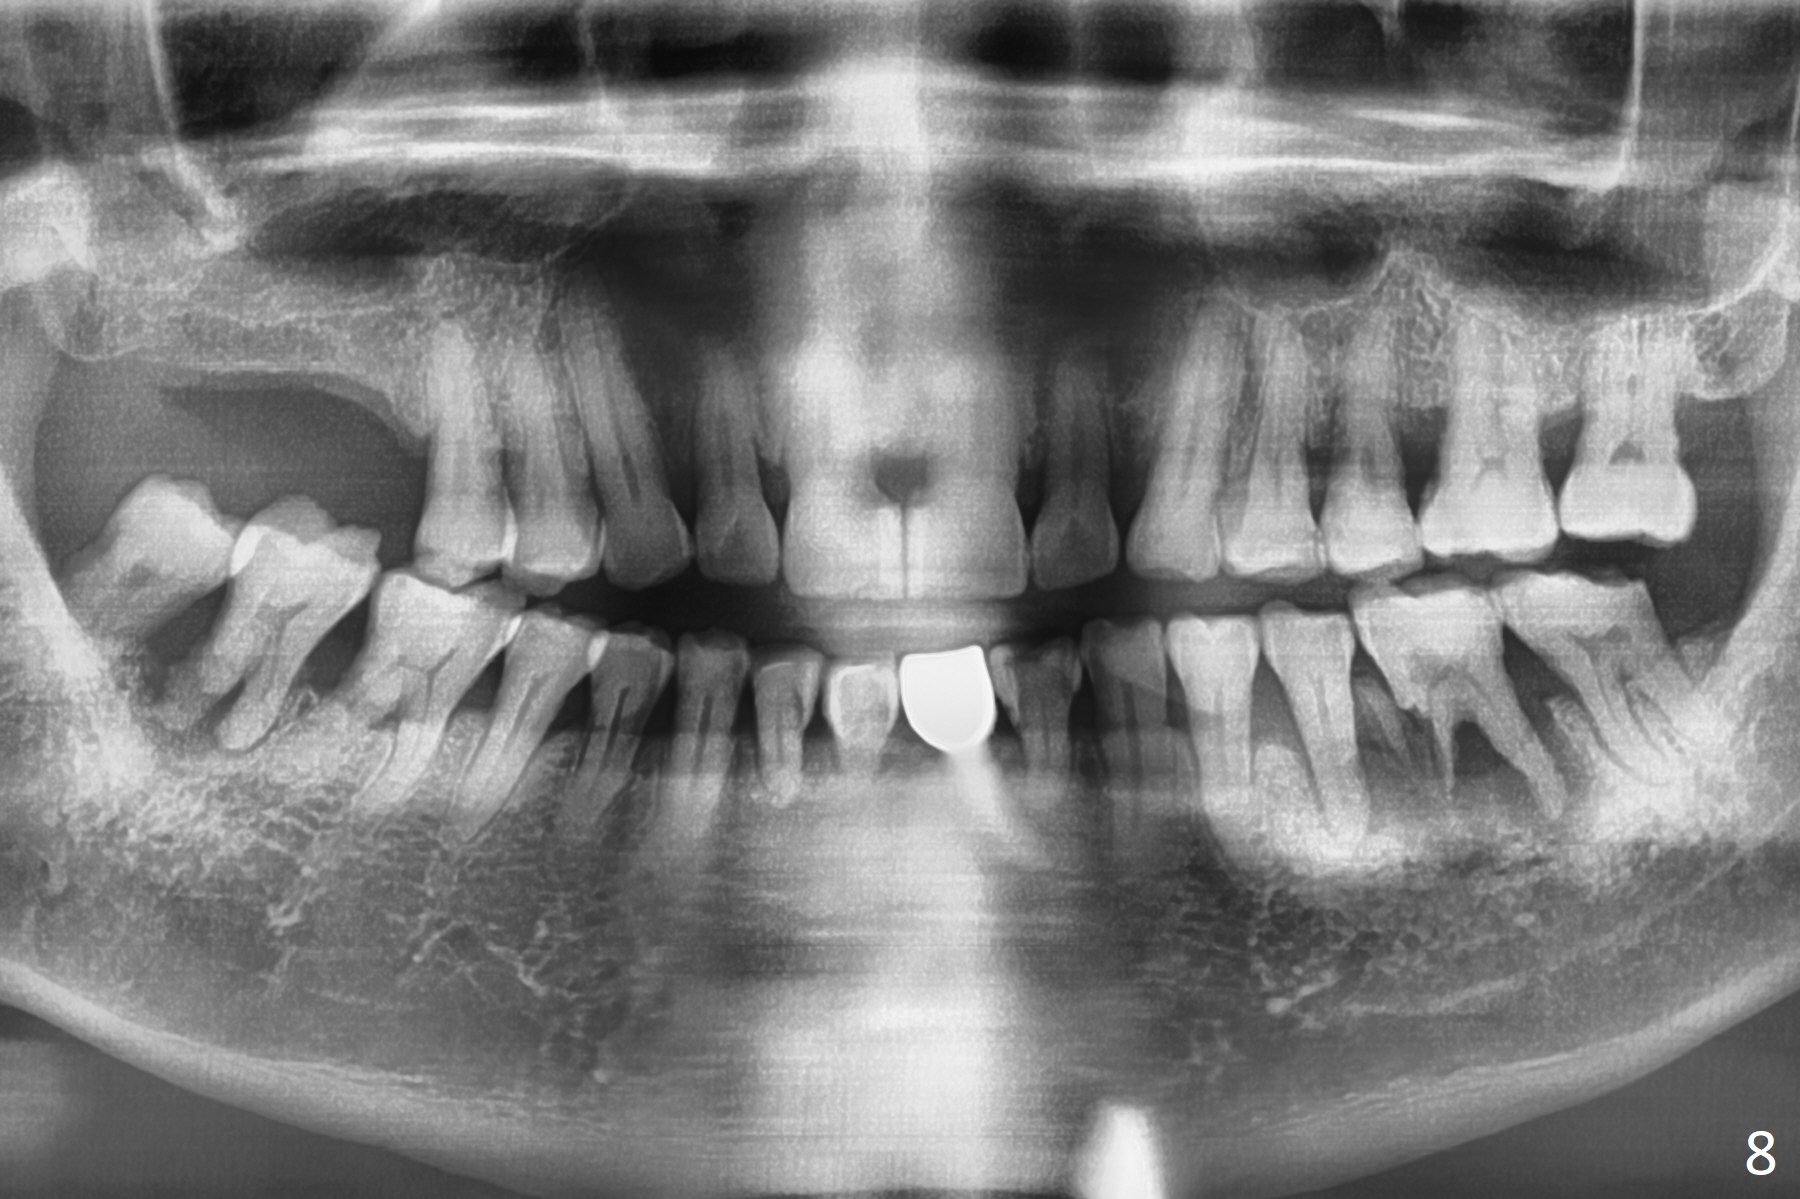

Bone loss (Fig.8) is more severe than 5 years earlier.